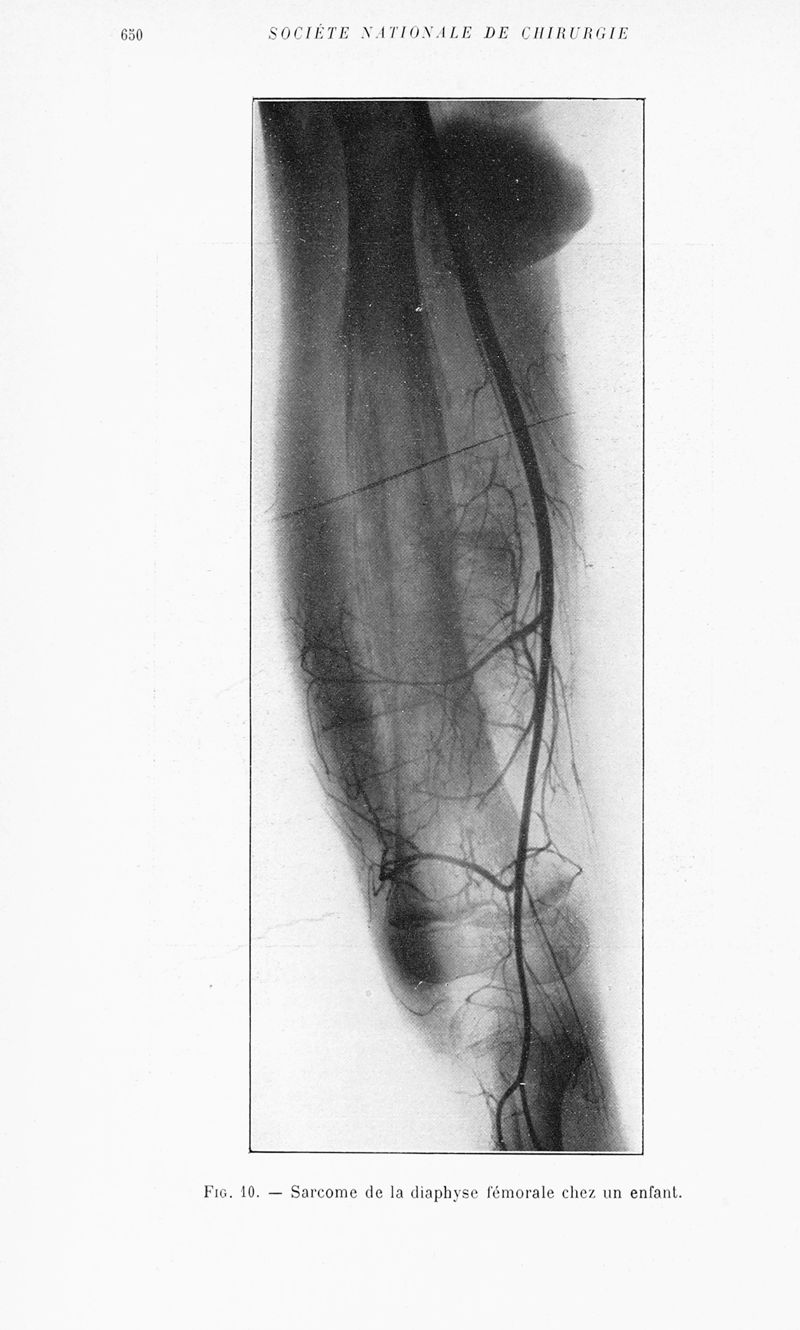

Bulletins et mémoires de la société nationale de chirurgie

Tome LVIII, 1932. - Paris : Masson, 1932.